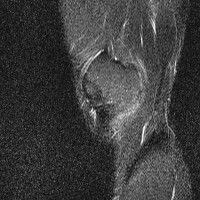

무릎 mri 간단히 봐주실 수 있으시나요 ㅠㅠ

안녕하세요 8년전 십자인대 수술하고 최근 무리한 운동에 무릎 불편감이 생겨서

mri 찍었습니다.

진단결과는 첫 찍은 병원에서 활액막염 이라는 진단을 받았습니다. 혹시 봐주실 수 있으실까요?

올라온 MRI가 단편적이라서 정확한 진단에 어려움이 있지만 십자인대에는 큰 이상이 있지는 않은것 같으며, 무릎관절내 물이 있는 것으로 보아 활액막염의 진단이 맞을 것 같습니다.

하지만 단편적인 영상이기 때문에 촬영병원에서 정확한 판독지 등을 받으시는 것이 좋겠습니다.